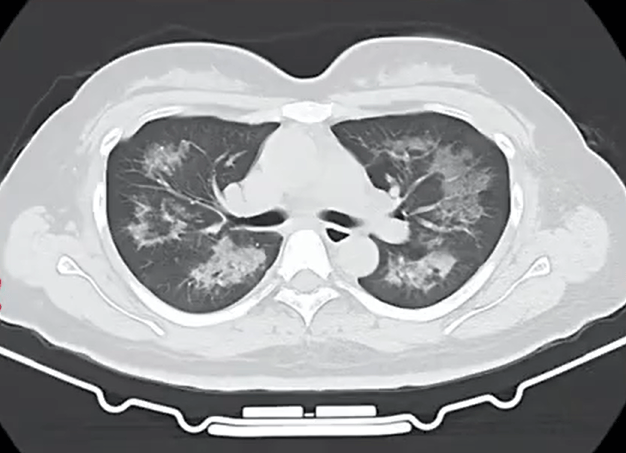

胸部CT进一步显示,她的双肺出现多发斑片状模糊影,被诊断为间质性肺炎虚拟货币矿机。医生判断,病因很可能与她近期长期接触的某类物质相关。经过医生反复细致地询问病史,小江才说出自己存在长期、频繁使用定妆喷雾的情况。